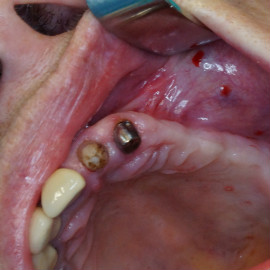

Pacjentka głosiła sie do naszego gabinetu do leczenia z osadzonym mikroimplantem w pozycji lewej dolnej dwójki. Siostrzany implant w pozycji prawej dolnej dwójki wypadł wcześniej, około 1,5 roku od implantacji. Odtworzono przedsionek i dziąsło rogowaciejące, osadzono dwa implanty, jednoczasowo z regeneracją kości. Dopiero na etapie ostatecznej rekonstrukcji protetycznej usunięto zachowany mikroimplant. To się nazywa motywacja do leczenia! Pacjentka przygotowywała sie na ślub prawnuczki :)